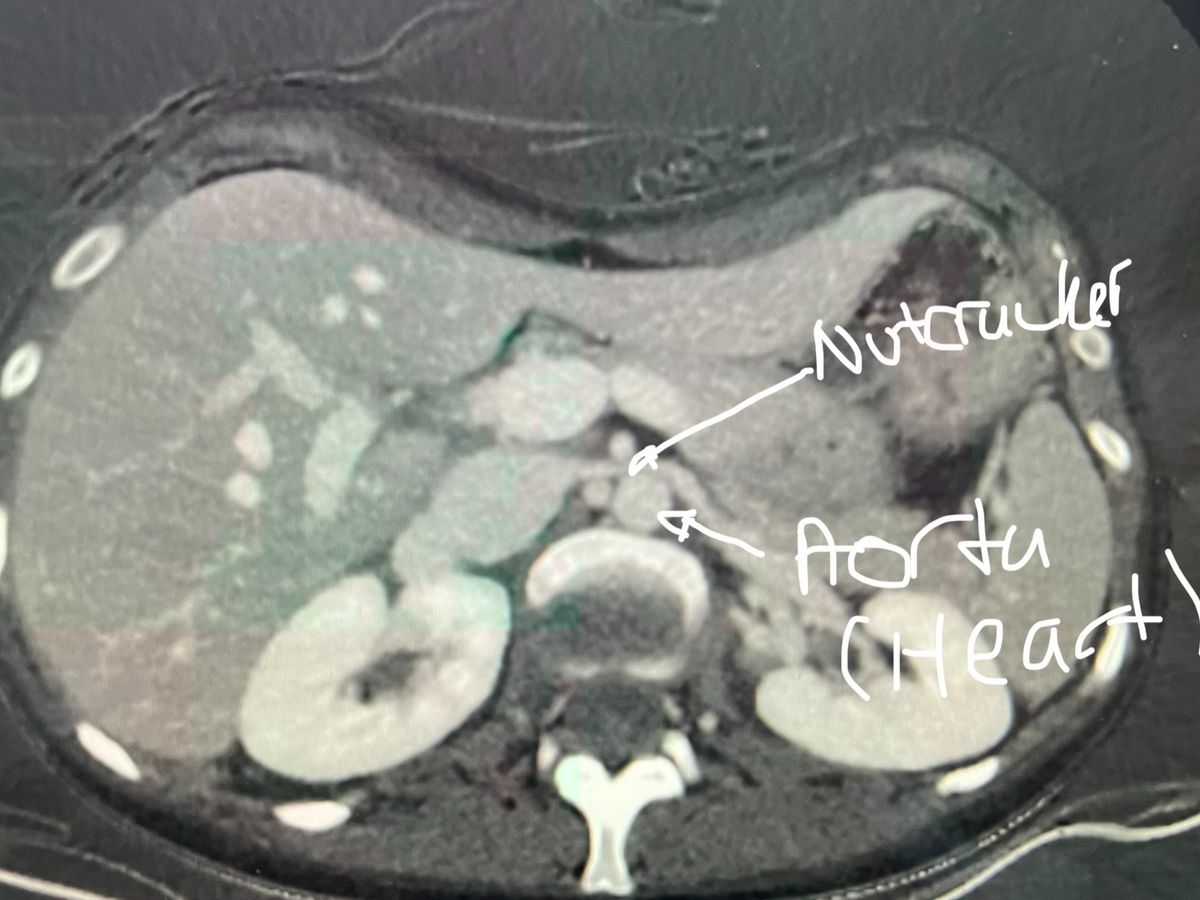

On March 4, 2026, my sister Margaret (MJ), a young adult, will undergo a groundbreaking procedure in London, Ontario. This complex, full-day surgery will be performed by a transplant team in London alongside a transplant surgeon flying in from Edmonton to treat severe left renal vein compression, known as Nutcracker Syndrome. In this condition, the vein responsible for draining blood from the left kidney becomes compressed between the aorta and the superior mesenteric artery (SMA), leading to impaired blood flow, increased venous pressure and compromised kidney function. This also causes an increase in blood pressure (144/108) and heart rate (up to 210bpm).

MJ is living with a rare and extraordinarily complex combination of four vascular compression disorders, which her team has unheard of all at once: Nutcracker Syndrome, a failed Median Arcuate Ligament Syndrome (MALS) surgery in 2023, Pelvic Congestion Syndrome, and May–Thurner Syndrome. These conditions have caused devastating effects on her health and quality of life, including over 30 pounds of unintentional weight loss and a critically low BMI.